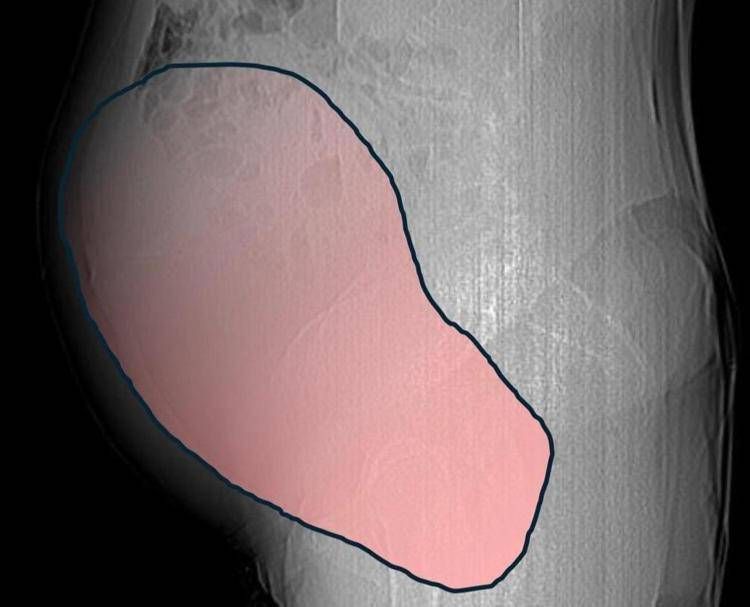

Una donna di 69 anni ha scoperto di essere affetta da un tumore ovarico di dimensioni eccezionali, paragonabili a quelle di una gravidanza gemellare a termine, solo quando il suo organismo ha improvvisamente iniziato a cedere. Per mesi la gigantesca cisti ovarica, con un diametro di circa 28 centimetri, è rimasta nascosta, senza dare segnali evidenti. La paziente non si era accorta di nulla. L’allarme è scattato quando la massa, associata alla presenza di una seconda neoplasia intestinale, ha iniziato a comprimere il colon, provocando sintomi acuti ed improvvisi fino ad una grave difficoltà intestinale non più ignorabile. A riferire la storia è l'ospedale Sant'Anna di Torino.

CTA